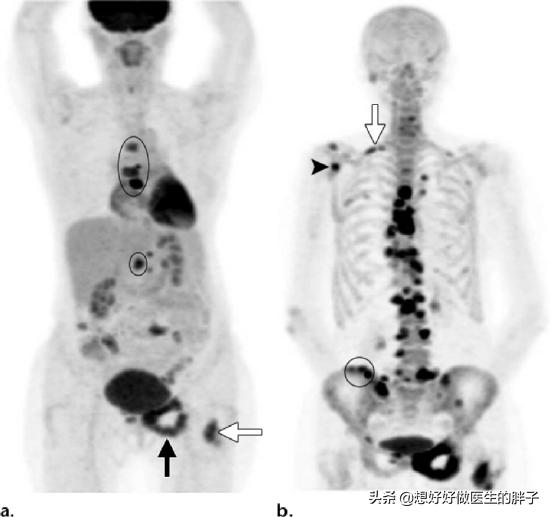

骨転移はどのような痛みに注意すべきですか?骨転移は悪性腫瘍の末期によく見られる症状で、体の他の部位にある原発腫瘍が血液やリンパ液の経路を通って骨に転移し、骨転移を形成することを指します。骨転移は、正常な骨組織が破壊され、腫瘍組織に置き換わっていることを示す。骨転移は病変の特異性により、溶骨型、造骨型、混合型の3つに分類される。骨転移の好発部位は中軸骨(脊椎、骨盤)、肋骨、下部骨幹部で、特に中軸骨が最も多く、これはこの部位の血液供給の特徴と関係しています。下の円のように骨転移が多発し、脊椎の状態が悪い。

がんの既往歴がなく、家計に余裕がある患者には、全身にがんの疑わしい病変がないかスクリーニングするためにPET-CT検査を行うことが推奨され、これにより腫瘍病変の有無、進行度、どのような転移病巣があるかなどを適切に判断することができる。

がんの既往があり、その時点で悪性度が高いと判断されれば、全身骨シンチで骨転移の有無を調べることができる。同時に、転移部位の骨破壊の程度を磁気共鳴検査で明らかにすることができる。